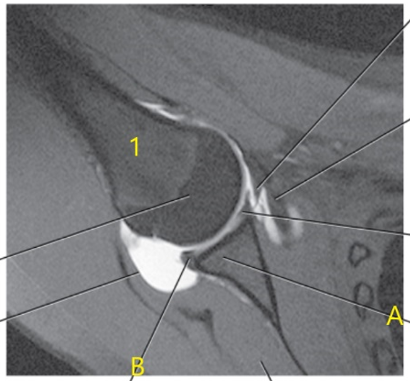

What anatomy is # 1 ?

Humeral head

What is letter c ?

Glenohumeral joint

Posterior glenoid labrum